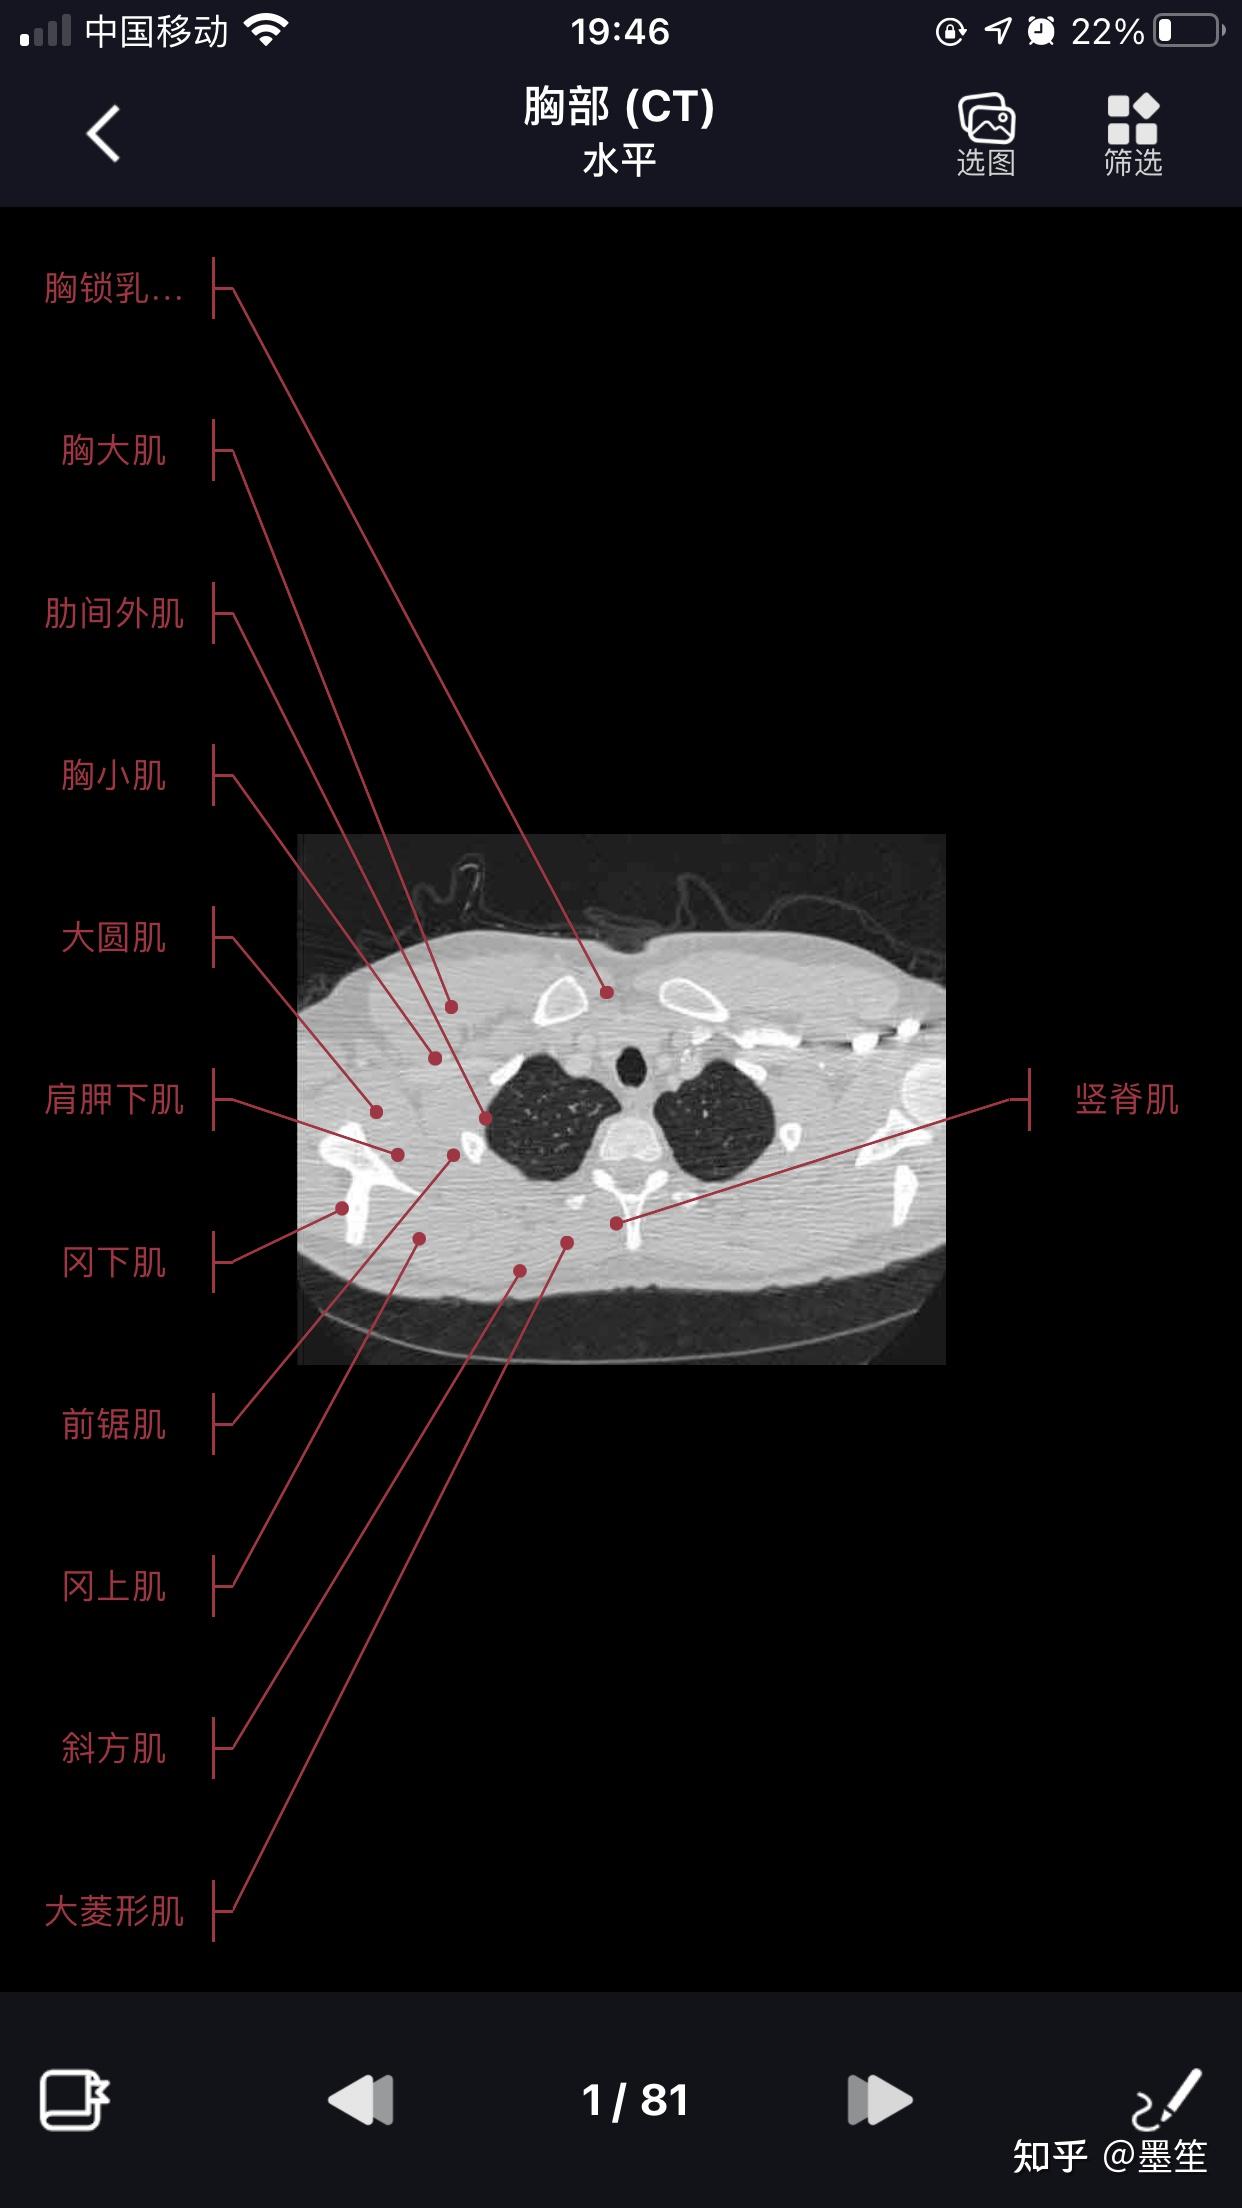

影像学习必备软件【影像解剖图谱】 - 知乎

图片尺寸1242x2208